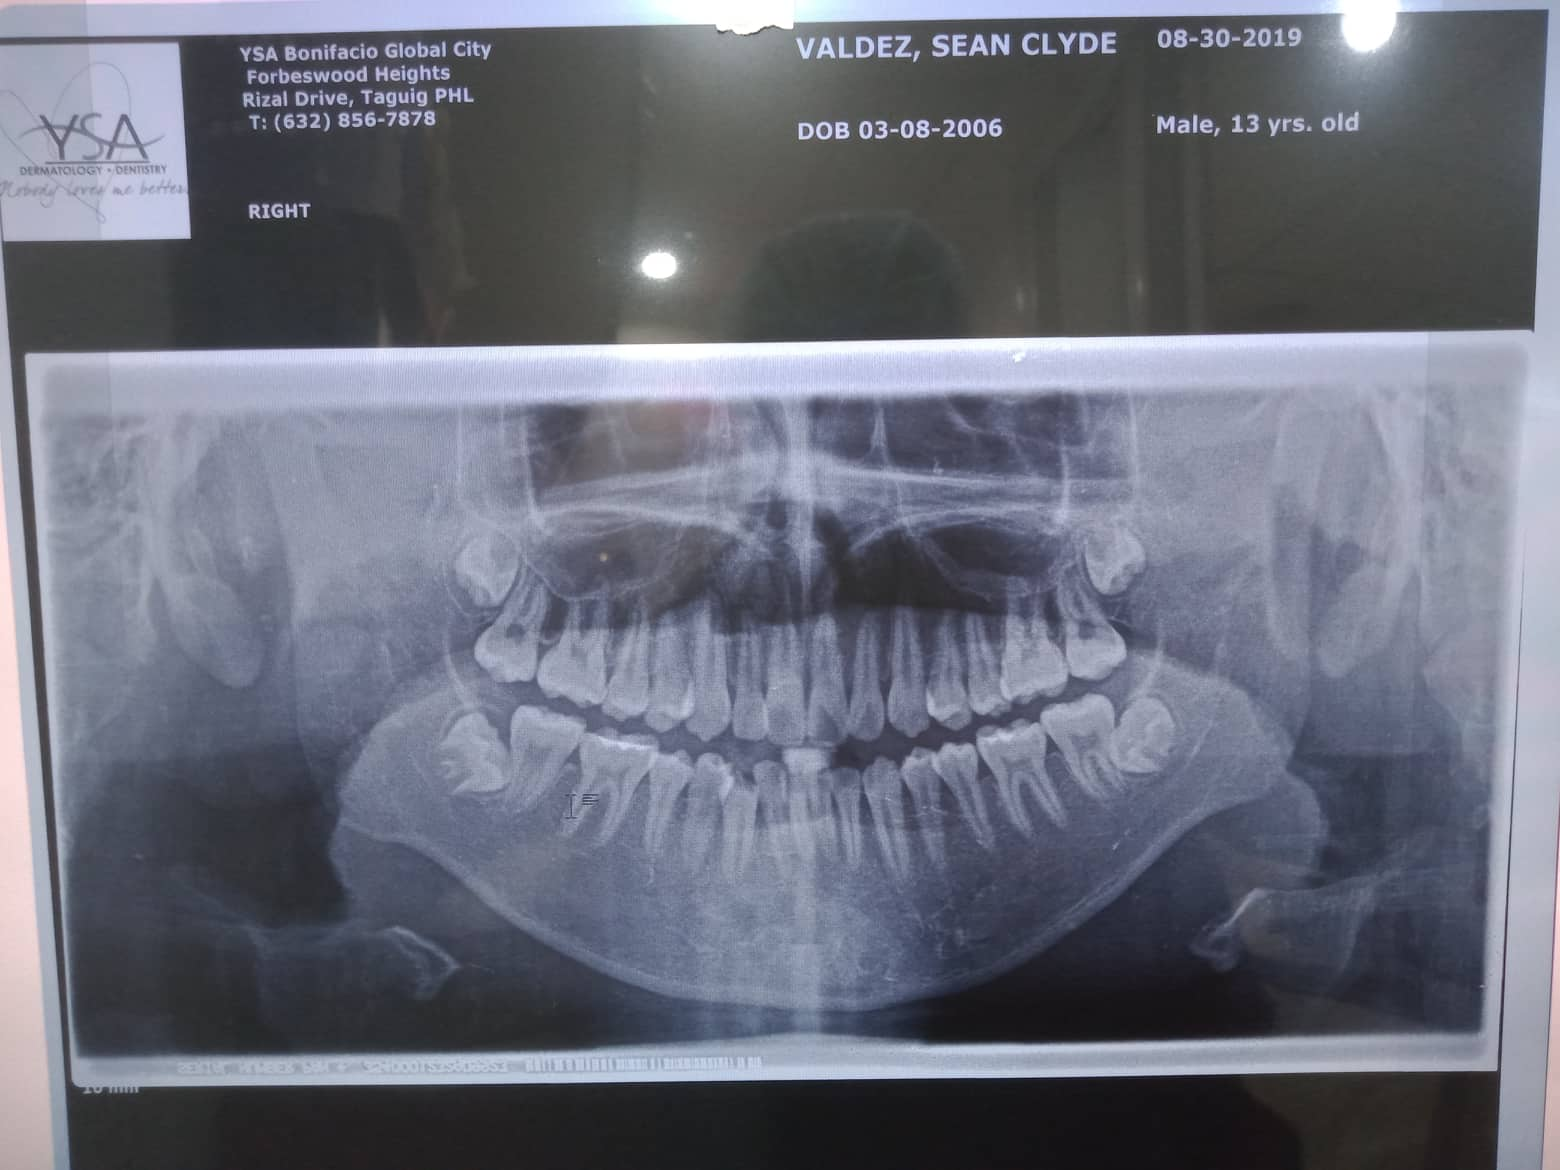

Edit Record Check our patient data records. Add patient information Patient Info Profile picture Last Name First Name Middle Name Birthdate Age Street Barangay City Country Zip Code Contact number Email Procedure 08/28/21- adj 14 nitiL/ 18ssU 11/06/21- 14 niti lower/ 18ss U/ double with 18ss extrude 4 anterior teeth to lock lower ant. canine to canine chipmunk 12/04/21- class 3 penguin./ chipmunk 13-14 to 44/ 23-24 to 34/ same wire 2/19/22- box elastic penguin 13-14-15 to 43-44/ 23-24-25 to 33-34 18 niti lower/ same wire upper next meeting reposition 4 anterior teeth- extrude 04/02/22- adj. 16 ss lower/ 16 ss upper canine to cnine elastic chipmunk ***odontec 5/21/22- 18 ss U/ 16 ss L criss cross elastic 14-45 to 13 -44 / 24-35 to 23-34 monkey class 3 elastic fox 7/23/22- chipmnk 13-14 to 45 same to oTher side reattached #23/ 16 16x16 ss U 8/27/22 - SAME WIRE/ RABBIT BOX 9/24/22 - SAME WIRE 11/18/22-adj/reattached 01/28/23 - same wire 1/27/23-adj 05/07/23 - Adj: L - chain 06/11/23-/same wire/Chain upper and lower/13-43-44 and 23-33-34 elastic chipmunk *FOR ODONTECTOMY 07/09/23-for removal/for odontec 38 adjustment same wire ligature wire upper 08/05/23- #38 Odontectomy/ Gel Foam/ Suture/ Horizontal Class C impaction 08/14/23- removal of suture 09/03/23- Removal of braces/Impression for UL/Retainer w/ Fluoride File 302097495_557515356127090_7489211668915153297_n.jpg File 2 302092195_479311170385623_8495452773336197942_n.jpg File 3 302927078_445401587362306_2447547542471112557_n.jpg File 4 File 5 File 6 File 7 File 8 File 9 File 10 File 11 File 12 File 13 File 14 File 15 File 16 File 17 File 18 File 19 File 20 Retain Record Retain Record Yes No Save Your Changes